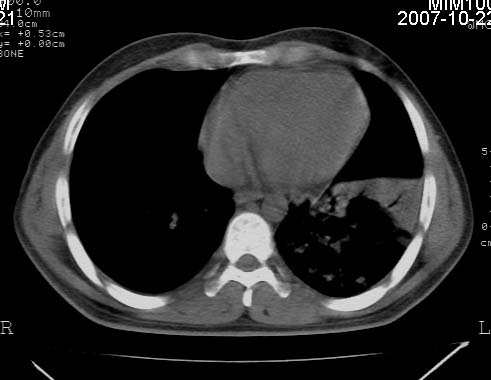

男,21岁,咳嗽、胸闷、乏力伴多汗二十余日、无明显发烧。患者一般情况好,为初三学生。

右肺上叶前段及左肺下叶多形性病变伴厚壁空洞,周边示树芽征.左肺下叶不张改变.

考虑;肺结核,不除外左肺下叶支气管内膜结核.

双肺继发性肺结核伴左侧空洞形成!不除外合并霉菌感染!(双肺多发病灶,左侧病灶形成空洞,并空洞内见壁结节。建议改变体位,观察空洞内结节情况,以便排除霉菌感染!)